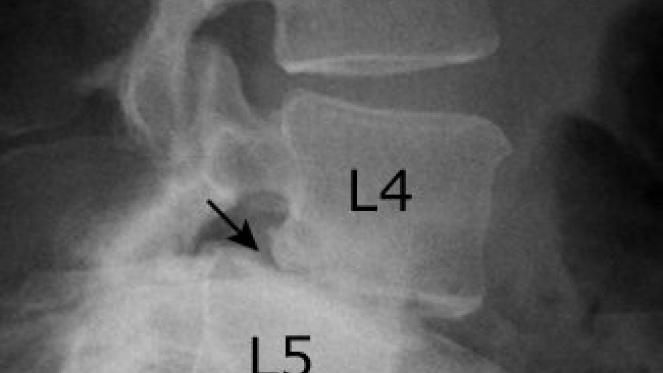

Gleitwirbel (Spondylolisthesis)

Spondylolisthesis wird in der Umgangssprache auch als Wirbelgleiten bezeichnet.

Sie ist in den meisten Fällen ein Ausdruck der Instabilität eines oder mehrerer Segmente der Wirbelsäule. Je nach Grad des Gleitens kann es zu Spinalkanalverengungen mit Nervenwurzelkompression und damit verbundenen Schmerzen und Ausfallerscheinungen (Sensibilitätsstörung, Lähmungen, Blasenmastdarmstörungen) führen.